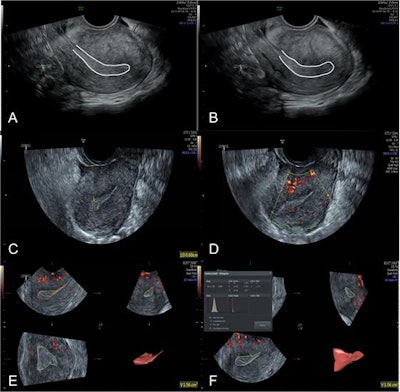

Ultrasound images of a subject in the AA group. (A, B) 2D grayscale mode; two images during observation. White curve, outline of endometrium. No endometrium peristalsis wave within 3 minutes; score, 1; (C) 2D grayscale mode; endometrial thickness, 6.0 mm; score, 1; endometrial type, type C; score, 1; (D) 2D color Doppler mode; a little blood flow in the subendometrium; score, 2; (E) 3D mode; EV, 1.56 cm3; score, 1; (F) 3D mode; VFI, 0.027; score, 2. Image courtesy of Insights into Imaging.Sixty-eight patients who had had an artificial abortion (AA group) and 70 women of childbearing age without any history of abortion (control group) were recruited between January 2018 and December 2018. All subjects received the examination of endometrium in the middle luteal phase (7-9 days after ovulation) with 2D grayscale ultrasound, 2D color Doppler ultrasound, and 3D ultrasound, and the quantitative scores were obtained and compared between the two groups.

The quantitative score of endometrial receptivity was 10.46 ± 2.99 in the AA group and 13.49 ± 2.21 in the control group, showing a significant difference (p < 0.05), the authors stated.